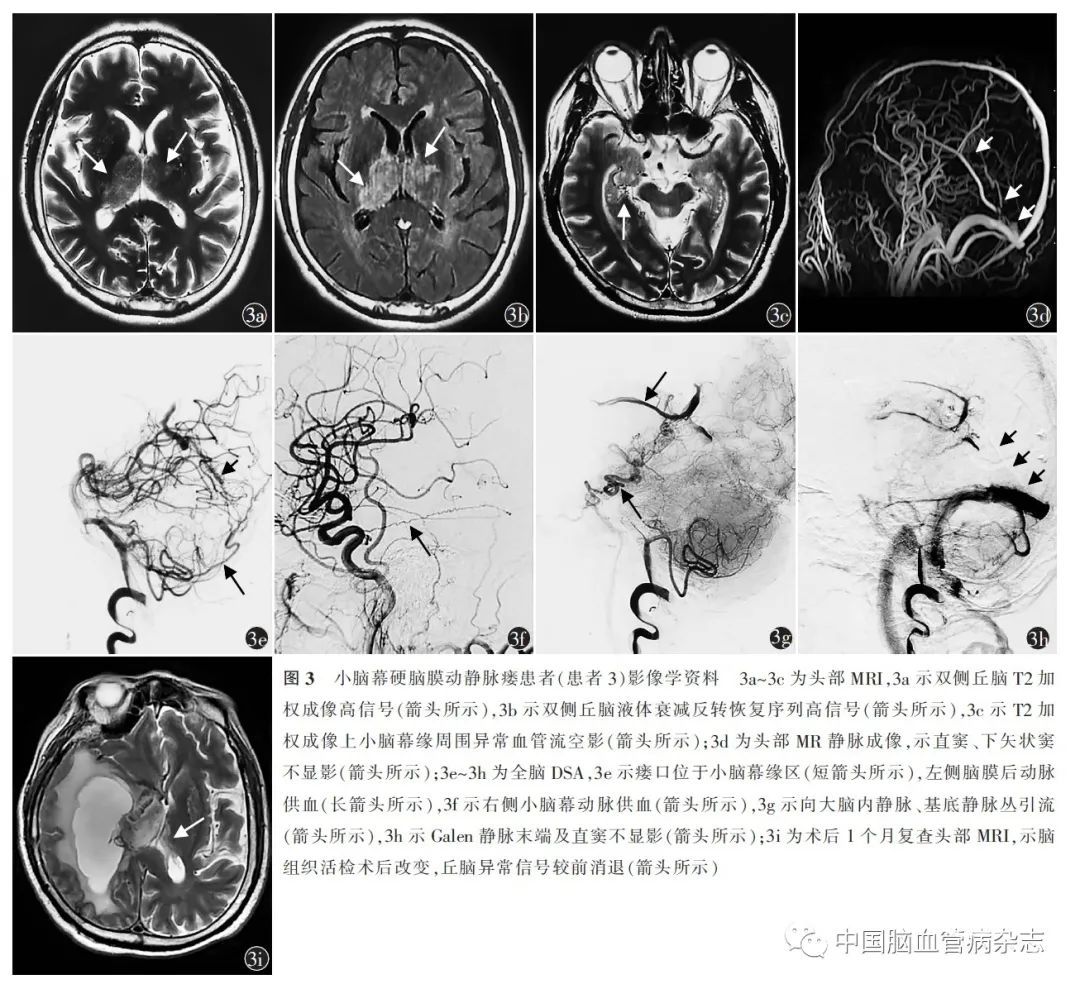

男,58 岁,因“头痛、精神行为异常2 月余,反应迟钝1 个月”于2021 年5 月18 日收入北京丰台右安门医院神经内科。患者于入院前2 月余出现后枕部持续胀痛,记忆力减退,言语错乱,无故傻笑,精神亢奋,伴视幻觉。于外院神经外科就诊,行头部MRI,示双侧丘脑不规则异常信号,T1加权成像低信号,T2 加权成像高信号,液体衰减反转恢复序列高信号,扩散加权成像等信号,病灶未见强化(图3a,3b)。头部MRA 示轻度脑动脉硬化表现。以“双侧丘脑胶质瘤”收入外院,行导航下显微镜下右颞枕开颅幕上深部肿瘤部分切除术,术后患者出现左侧肢体无力。病理报告示丘脑组织未见肿瘤细胞,不除外小血管病变可能。患者入院前1 个月出现淡漠,反应迟钝,睡眠增多。转外院神经内科,行腰椎穿刺术,压力210 mmH2 O,脑脊液无色透明,白细胞2 × 106 个/ L,蛋白0.65 g/ L,葡萄糖3. 4 mmol/ L,氯化物120. 5 mmol/ L,寡克隆区带阴性,自身免疫性脑炎相关抗体、副肿瘤综合征相关抗体均阴性。头部MR 波谱示右侧丘脑病灶N-乙酰天门冬氨酸/肌酸:1. 05,左侧相应部位N-乙酰天门冬氨酸/肌酸:1.66,右侧丘脑病灶胆碱/肌酸:1. 51,左侧相应部位胆碱/肌酸:1. 12。拟诊为“免疫相关性脑炎”,给予丙种球蛋白30 g,1 次/ d ×5 d,甲泼尼龙琥珀酸钠500 mg,1 次/ d ×3 d,每3 天剂量减半,患者症状无缓解。患者既往有高血压病史6 年。入院体格检查:意识清楚,言语流利,定向力、理解力、记忆力、计算力减退,MMSE 评分17 分(高中学历),脑神经功能检查(- ),左侧肢体肌力Ⅱ级,右侧肢体肌力Ⅴ级,腱反射(+ + ),左侧Babinski 征(+ ),脑膜刺激征(- )。外院头部MRI 阅片发现,双侧小脑幕缘附近可见异常增粗血管流空影(图3c)。初步诊断:双侧丘脑病变性质待查。辅助检查:头部MR 静脉成像示直窦、下矢状窦未显影(图3d)。全脑DSA 示小脑幕缘区DAVF,左侧脑膜后动脉、右侧小脑幕动脉供血,向大脑内静脉、基底静脉丛引流,Galen 静脉末端及直窦未显影,考虑血栓形成(图3e ~ 3h)。入院第8 天行经动静脉联合血管内栓塞术,经颈内静脉直窦球囊扩张+直窦内支架置入术,术后给予抗凝治疗,依诺肝素钠注射液4 000 IU,1 次/12 h,连续3 周,随后改为利伐沙班20 mg,1 次/ d,1 周后剂量减为10 mg,1 次/ d。住院16 d 出院。出院诊断:TDAVF、直窦血栓形成。术后1 个月复查头部MRI,示丘脑异常信号较前消退(图3i)。术后2 个月门诊随访无复发,认知功能障碍较前改善,MMSE 评分23 分,遗留左侧肢体无力,肌力Ⅲ级。

TDAVF 诊断需仔细分析影像资料。CT 与MRI 等检查可发现继发性改变,对诊断有提示意义,包括:(1)静脉引流区域血管源性水肿,见于丘脑、脑干、小脑、颈髓等部位,CT低密度,MRI T2 加权成像和液体衰减反转回复序列高信号,通常无扩散受限[14],扩散加权成像等、低或稍增高信号,表观扩散系数图高信号,水肿可长时间存在,可伴脑实质、蛛网膜下腔出血,出血部位多远离瘘口;(2)MRI T2 加权成像可见引流静脉扩张导致的异常血管流空影,呈“条索样”、“虫蚀样”血管流空影或扩张血管团,常见于小脑幕裂孔附近、脑干和脊髓表面;(3)如伴静脉窦逆行引流或合并IVST,MR 静脉成像可见直窦、横窦、乙状窦不显影[11,15]。患者1 颈髓、延髓水肿,髓周血管流空影,患者2 和3 双侧丘脑对称性水肿,直窦不显影,患者2 伴丘脑出血,患者3 双侧小脑幕裂孔附近异常血管流空影,均对TDAVF 诊断起到提示作用。非侵入性血管检查MRA、CT 血管成像可显示血管异常,如增粗迂曲的引流静脉、静脉窦早期显影等。受分辨率限制,MRA 阴性不足以排除DAVF。CT 血管成像对DAVF 影像表现的敏感度62% ~ 96% ,特异度79% ~ 94% [16]。患者2 和3 行MRA 检查,但未发现提示TDAVF 的血管异常,3 例均未行CT 血管成像,是延迟诊断的原因之一。最终的确诊依靠DSA,DSA 可明确显示瘘口位置,供血动脉来源及静脉引流方式,是诊断DAVF 的“金标准”及制定治疗策略的依据。